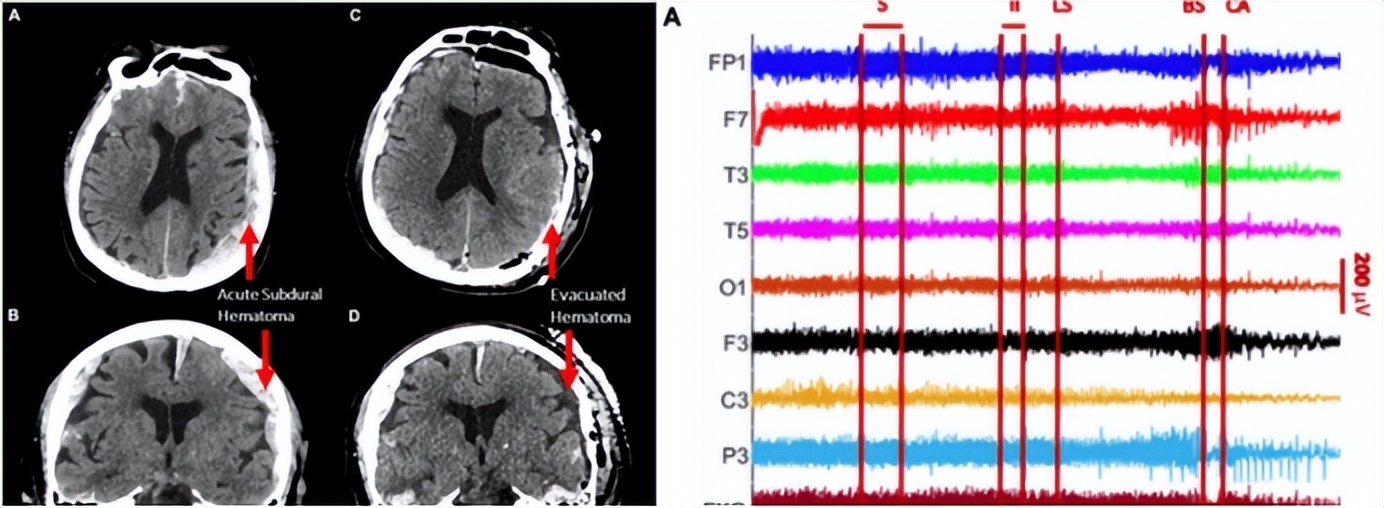

但是,在家属签署放弃治疗协议之前,医院也是曾经尝试着进行过抢救的,这也就导致这名男性患者被连上了EEG(脑电图),也正是因为抢救过程中的EEG,才会让科研人员意外获得了这份珍贵的“濒死脑电波”。

那么,这名男性患者在死亡的一瞬间,他究竟在想些什么事情呢?通过对EEG记录的数据研究分析,科学家们惊讶地发现,这名男性患者在死亡瞬间,出现了“记忆闪回”,简单来说,就是他一生中的经历,都在死亡的这一瞬间,好像是“走马灯”一般,在他的大脑中不断闪现,一直到他彻底死去。